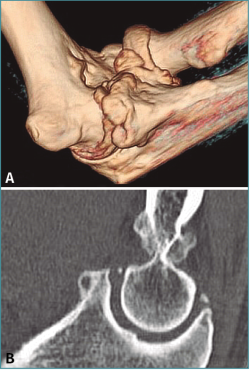

Método: hemos revisado 38 pacientes con codo rígido postraumático o degenerativo que se trataron mediante artrolisis artroscópica entre 2013 y 2016, con un seguimiento medio de 25 meses (38-15). Según la etiología de la rigidez, clasificamos a los pacientes en 2 grupos: grupo 1, los pacientes con rigidez por patología degenerativa del codo, y grupo 2, los pacientes con rigidez postraumática. Clasificamos la rigidez siguiendo la escala de Morrey y utilizamos la escala funcional Mayo Elbow Performance Index (MEPI), que evalúa el dolor, la movilidad, la estabilidad y la función del codo pre- y postoperatoriamente. Describimos los procedimientos artroscópicos realizados en cada paciente, que incluyen la sinovectomía, el desbridamiento de tejido fibroso, la capsulectomía anterior y/o posterior, la resección de osteofitos en la parte anterior y posterior del codo, la extirpación de cuerpos libres y la liberación “abierta” del nervio cubital.

Method: a review was performed on 38 patients with stiff elbow due to degenerative or post-traumatic reasons, and who were treated by arthroscopic arthrolysis between 2013 and 2016, with a mean follow-up of 25 months (38-15). Elbow stiffness was classified following the Morrey scale and the Mayo Elbow Performance Index (MEPI) functional scale was used to evaluate pain, mobility, stability and elbow function pre- and post-operatively. The arthroscopic procedures performed on each patient are described, including synovectomy, debridement of fibrous tissue, anterior and/or posterior capsulotomy, resection of osteophytes in the anterior and posterior part of the elbow, extirpation of loose bodies and open release of the ulnar nerve.